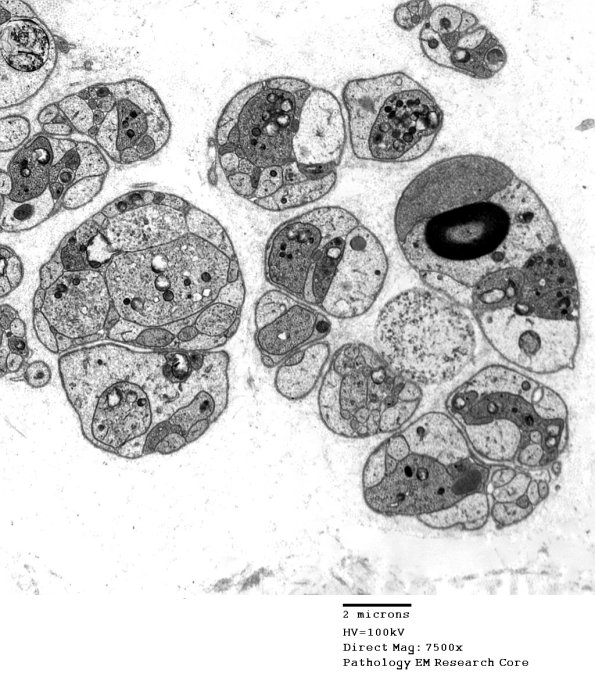

3B1,2 Numerous regenerative axons in Schwann cell tubes. In most cases axons and Schwann cell processes can be separated on the basis of density, shape and contents but small processes may not be separable morphologically. Schwann cell cytoplasm in this case is pale and denser processes appear to be axons. (electron micrographs)